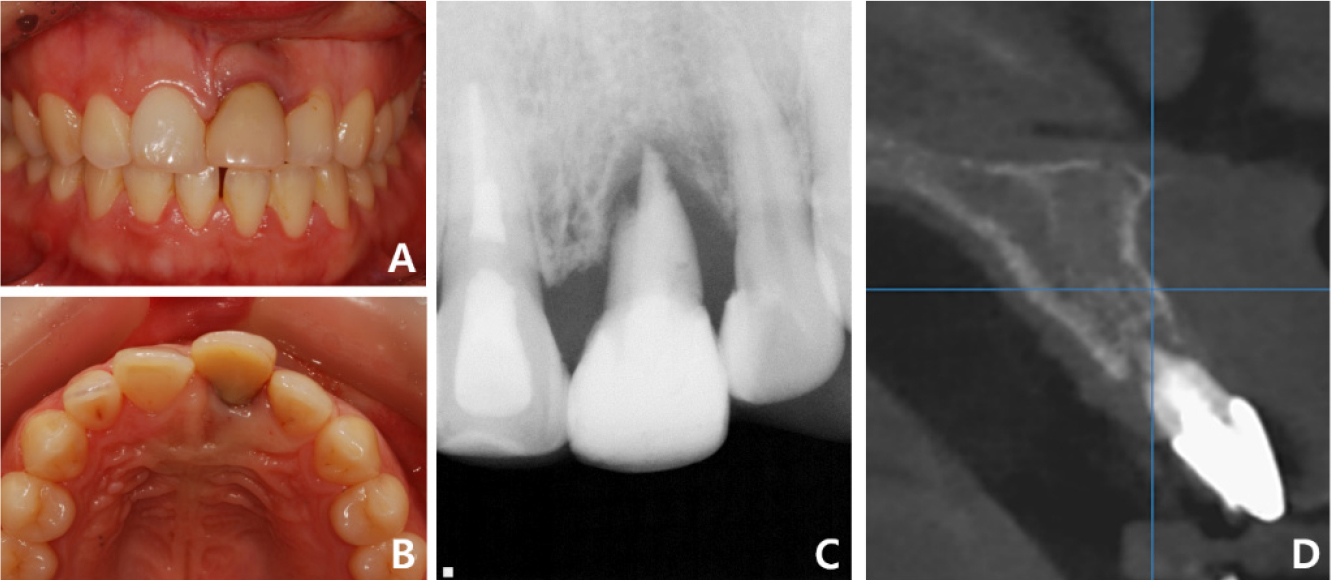

A 21-year-old healthy, nonsmoker woman reported to the Department of Prosthodontics at Gangnam Severance Dental Hospital to request an aesthetic anterior prosthesis to replace the old crown of her upper left central incisor. Clinical examination revealed periodontal pockets up to the apical third and moderate-to-severe mobility (Fig. 1A, 1B). Radiographic examination revealed root resorption of the incisor and severe resorption of the surrounding bone (Fig. 1C). Cone-beam computed tomography (CBCT) was performed to measure the bone volume and plan the bone graft owing to vertical and horizontal bone loss (Fig. 1D). Since the patient was young, interested in an aesthetic smile, and did not want any invasive treatment at other sites, implant placement with an allogeneic block-bone graft was planned. Patient consent was obtained for all procedures.

Fig. 1.

Case 1: Intraoral and radiographic views at the patient’s first visit. (A) Periodontal disease is observed in tooth #21, (B) Pathologic migration of tooth #21 toward the labial side, (C) Periapical radiograph shows external root resorption in tooth #21, (D) Sagittal cone-beam computed tomography image shows alveolar bone resorption around tooth #21.